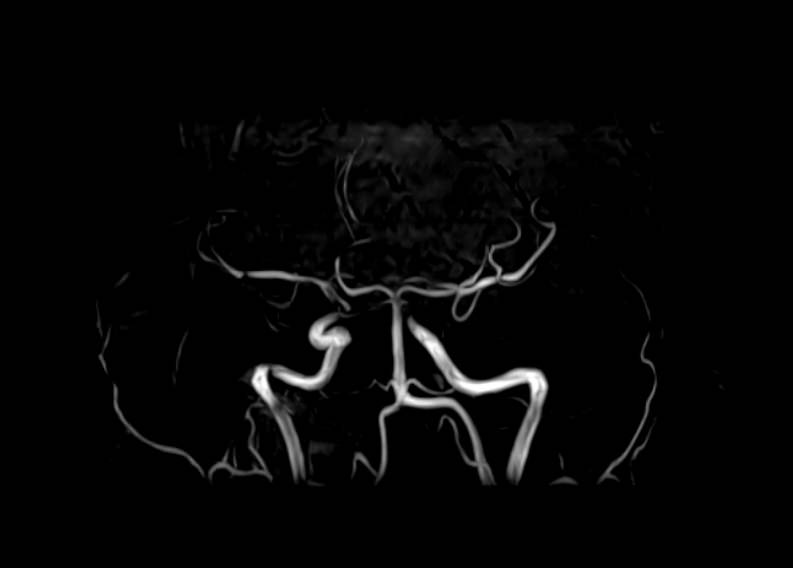

МР-ангиография — неинвазивный безопасный метод исследования для диагностики патологии сосудистой системы головы и шеи. Магнитно-резонансная ангиография позволяет получить трехмерное изображение кровеносных сосудов, оценить анатомическое строение сосудистой системы головного мозга и функциональные особенности кровотока.

С помощью электромагнитных волн томограф послойно сканирует структуры исследуемого органа, затем посредством компьютерных программ преобразует полученные данные в трехмерное изображение. При этом на снимке видна только сосудистая система без окружающих тканей. Таким образом, сканирование в режиме ангиографии позволяет визуализировать артерии и вены головного мозга без контрастирования. Однако в некоторых случаях для более точной диагностики может потребоваться введение контраста. Для этого используются гадолиний содержащие контрастные вещества. Дополнительное контрастирование дает возможность визуализировать мельчайшие сосуды и выявить нарушения микроциркуляции головного мозга.